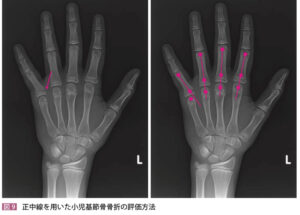

| 検査 | 【身体所見】 手関節発赤腫張、フォーク状変形、橈側の圧痛、回内回外制限 【画像検査】 Xp:手関節2方向で撮像し骨折線を探す、尺骨茎状突起や舟状骨も確認する 小児の場合は若木骨折を疑う(左右確認) 小児で転位が強い場合はSalter-Harris分類を行い手術の可能性があれば即整形コンサルト![]() |

小児の場合は若木骨折を疑う(左右確認)

小児で転位が強い場合はSalter-Harris分類を行い手術の可能性があれば即整形コンサルト